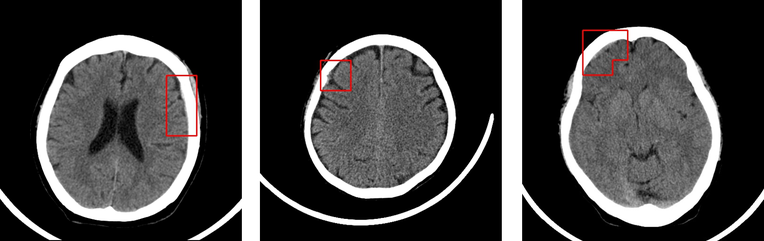

Creado para su uso por los departamentos de emergencias, Deep01 dice que su software puede detectar hemorragia intracerebral aguda con una tasa de precisión del 93% al 95%, en 30 segundos.